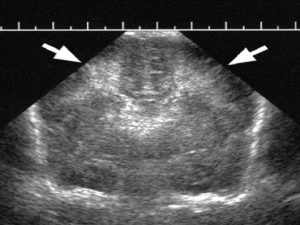

Як виглядає на УЗД

Нижче представляємо вашій увазі знімок УЗ-діагностики, на якому є гематома на матці.